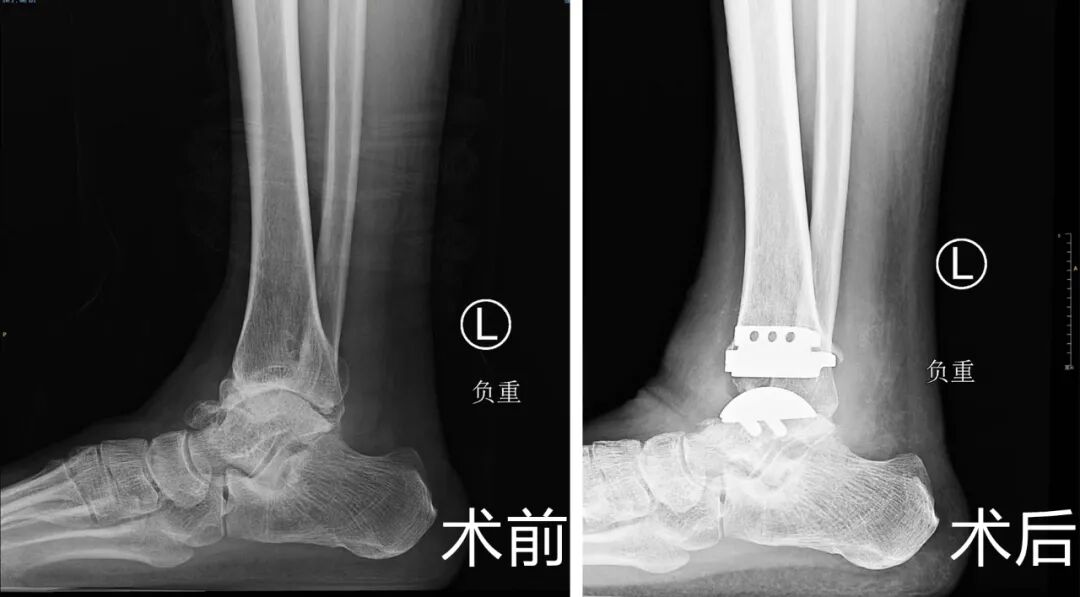

十多年前,赵大叔左脚崴了一次,疼了很久,但一直没有正规治疗过,也就敷敷膏药,休息几天,慢慢的踝关节状况越来越差,最后拖成了终末期踝关节炎。当时来院的时候赵大叔脚部情况很差,距骨坏死,外侧副韧带有陈旧的疤痕,踝关节的周围都是骨赘,而且软骨的损伤是比较重的,踝关节正常的关节面已经不存在了,每走一步都疼痛不已。

对于终末期踝关节炎,临床治疗有两种方法,一是关节融合,就是将关节固定,患者踝关节不能再曲伸,二是全踝关节置换,可以保留踝关节功能。经过沟通,大叔选择了可以保留踝关节活动的全踝关节置换术。

这次家访的时候,赵大叔通过锻炼已经具备了踝关节正常跖曲和背伸的功能,曹广超主任通过查体发现小腿肌肉力量仍有不足,后续还要通过锻炼来加强小腿肌肉的力量。